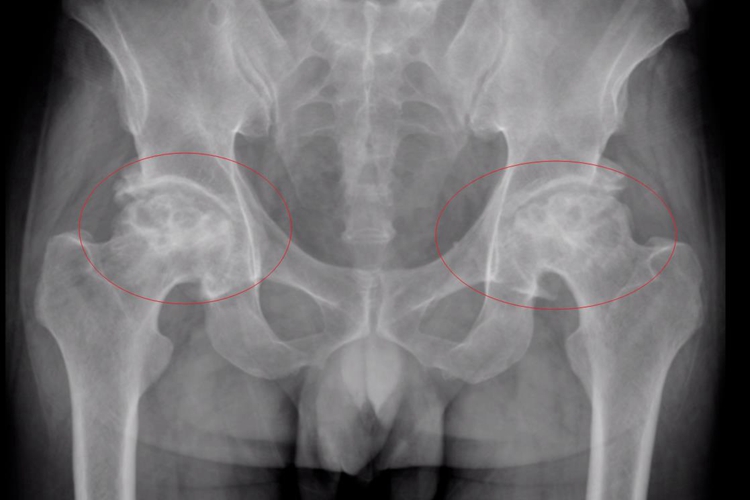

Ⅱ期(股骨头修复期)

X片显示股骨头外形完整,关节间隙正常,股骨头负重区关节软骨下骨质密度增高,周围可见点状及斑片状密度减低区及囊性改变,病变周围常见一密度增高的硬化带包绕着上述病变区。